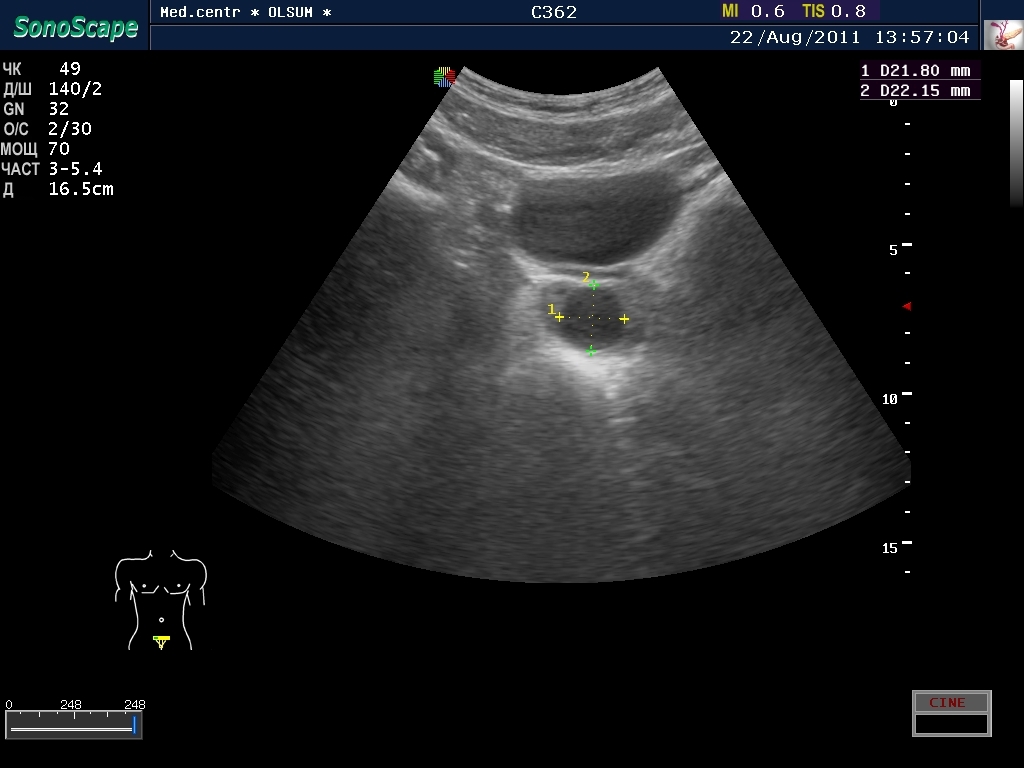

Кисты простаты диагностируются на сонограммах за счет типичной локализации и характерных очертаний. Иногда для установления окончательного диагноза проводят трансректальную биопсию под контролем ультразвука.

Для уточнения диагноза выполняют ультразвуковое исследование с трансректальным датчиком.

При выполнении ультразвуковой диагностики трансректальным доступом лучше видны кисты с диаметром больше 10 мм, при обычном, трансабдоминальном исследовании, маленькие образования диагностировать невозможно.